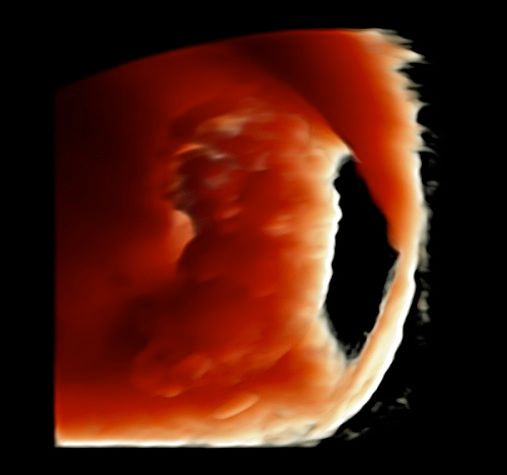

Foto e video

• Ecocardiografia fetale